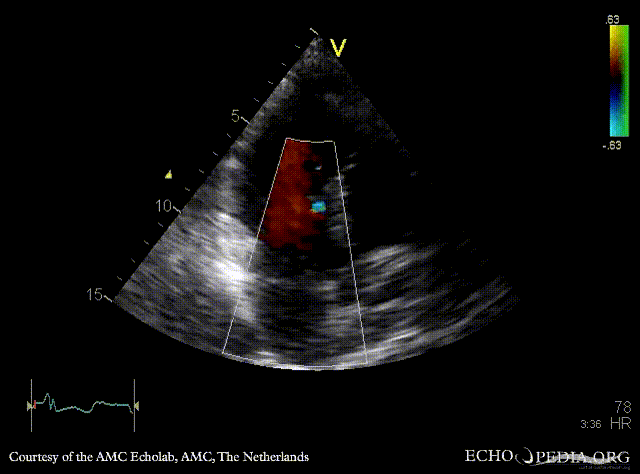

E00502.gif E00503.gif

PLAX: concentric hypertrophy of left ventricle, SAM of AMVL PLAX with Color Doppler: high velocity turbulent flow in LVOT